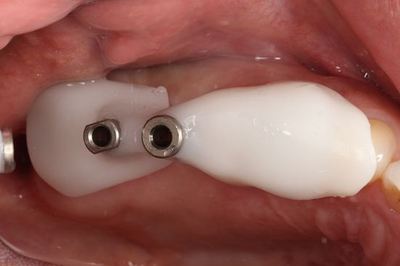

無事埋入を終えました。

挿入ジグを外しました。インプラントネックが見えています。

ヒーリングキャップのセットを終えました。

オレンジ色に見えるのは固着防止用に用いた表面麻酔軟膏です。

インプラントはスイスのストローマンインプラントです。

スタンダードプラスインプラントΦ4.1とΦ4.8 長さは同じ8mmです。